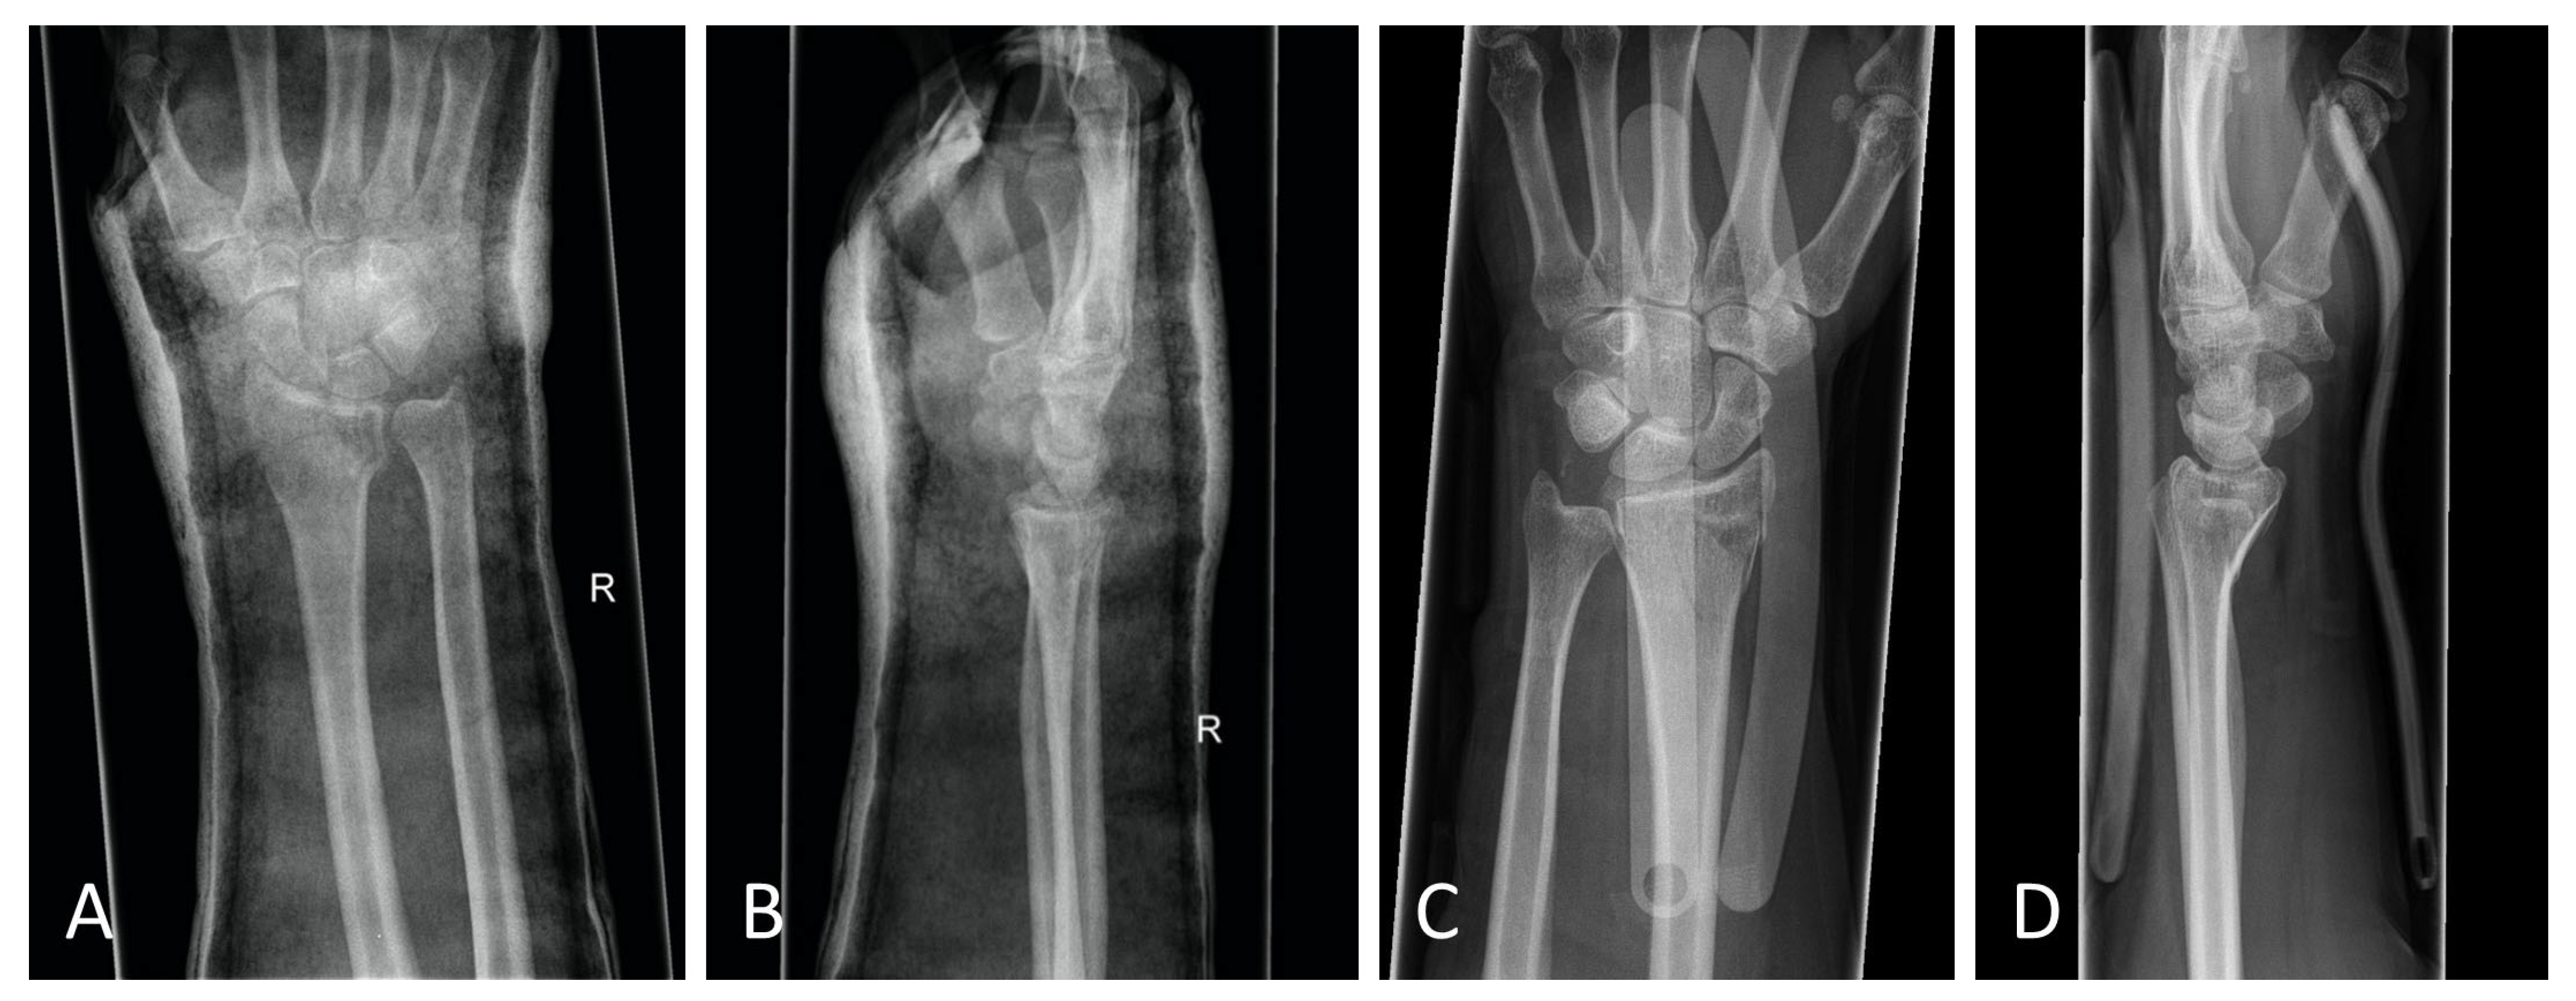

The standard treatment approach in our Level I trauma center was not altered by the study protocol, except from the placement of the orthosis. In our approach, we were able to adjust the orthosis used immediately during finger-trap traction and show that there was no increase in secondary dislocations on the radiographic and CT control imaging and, moreover, that diagnostic procedures were in no way restricted when the orthosis was in place. The quality of detail was not limited in any way in the lateral projection, very less in the posteroanterior view (Figure 6A–D). Additionally, the use of the orthosis did not affect the CT scan. As shown in Figure 7, there are no metal artifacts induced by the aluminum splints. Hence, modern orthoses enable comprehensive radiographic diagnostics.

Figure 6.

(A) Posteroanterior radiograph with cast. (B) Mediolateral radiograph with cast. (C) Posteroanterior radiograph with orthosis. (D) Mediolateral radiograph with orthosis. All radiographs were taken after reduction before surgery.